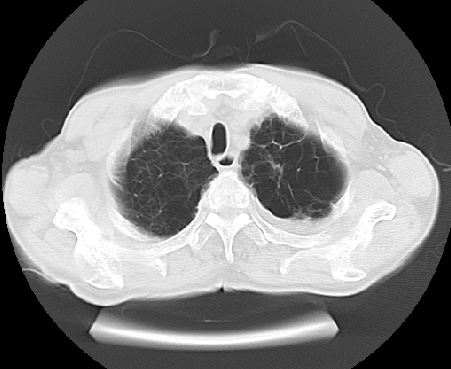

以下是引用ct诊断高手在2009-5-29 13:50:00的发言:[br]考虑左侧中央型肺癌,阻塞性肺炎伴肺不张。纵隔淋巴结转移。慢支 肺间质纤维化肺气肿。左侧胸腔积液。左侧肋骨转移?

以下是引用hhcckk在2009-5-29 14:58:00的发言:[br]左上周围型肺癌,左肺门、纵隔淋巴结转移,左侧胸腔积液,左侧肋骨转移[br]